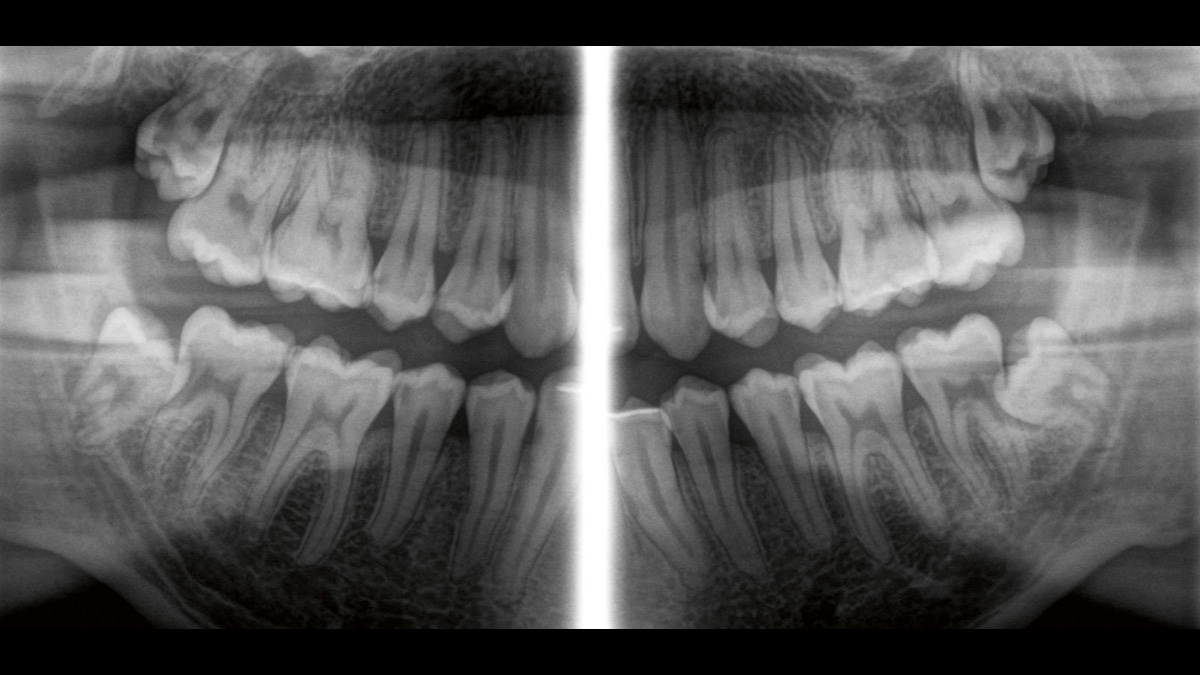

Der 2D/3D Power Performer Orthophos SL ist eine großartige Wahl für alle, die einfach mehr wollen. Der integrierte Direct Conversion Sensor (DCS) wurde für anspruchsvolle Bildqualitätsstandards entwickelt und bietet detaillierte Daten. Der intelligente Autofokus liefert automatisch fokussierte Panoramabilder mit hervorragender Gesamtschärfe. Orthophos SL bietet höchsten Bedienkomfort durch automatische Positionierung, eine anwenderfreundliche, intuitive Bedienung mit dem EasyPad und ein individuell einstellbares Umgebungslicht für ein exklusives Erscheinungsbild.

Der Direct Conversion Sensor erfüllt besonders hohe Standards für die 2D-Bildgebung

Der Autofokus erzeugt aus mehreren tausend Einzelbildern automatisch eine beeindruckende scharfe Panorama-Röntgenaufnahme

Der Direct Conversion Sensor (DCS) hat den Standard der Panorama-Bildgebung neu definiert. Röntgenstrahlen werden direkt in elektrische Signale umgewandelt – im Gegensatz zu herkömmlichen Systemen gibt es keinen Signalverlust durch Lichtumwandlung, was eine verbesserte Bildgebung ermöglicht. Das Ergebnis sind Bilder mit einer sehr hohen Schärfe, selbst bei niedriger Dosis.

Eine Röntgenaufnahme muss sofort diagnostizierbar sein. Der Autofokus hilft dabei erheblich. Orthophos SL erfasst mehrere tausend Einzelbilder in einem Zyklus und erkennt automatisch scharfe Bereiche, um ein gleichmäßig scharfes Gesamtbild zu erzeugen. Der intelligente Autofokus erfordert keine manuellen Arbeitsschritte vor und nach der Erfassung.